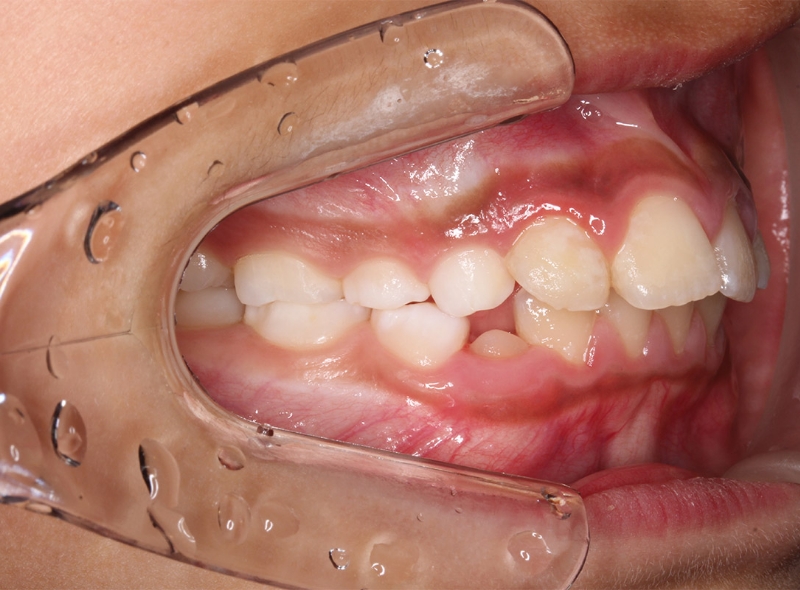

CASE 小児の矯正(叢生)

Before

After

| 年齢 | 11歳(治療開始時) |

|---|---|

| 性別 | 男性 |

| 症状 | 叢生(歯並びがガタガタしている) |

| 治療法 | |

| 費用 | 495,000円(税込み) |

| 通院回数 | 症例による |

| リスク・副作用 | 特になし |

| 備考 | やや遅い治療開始ではあったが、本人の頑張りによりブラケット(ワイヤー)を使わず、歯も抜かずに治療完了。 |